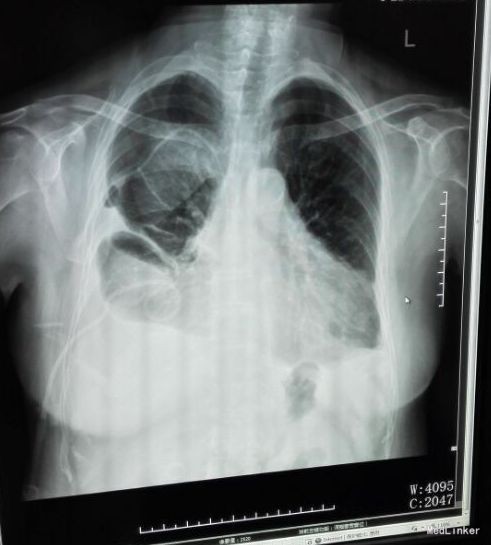

入院查体:体温:36.3℃(X),呼吸:25次/分,脉搏:105次/分,血压:160/80mmHg。神志清楚,平车入室,查体合作。全身皮肤未见皮疹,未见皮下出血点,浅表淋巴结未扪及肿大,咽充血++,扁桃体Ⅰ度肿大,可见滤泡,未见脓点,颈软,气管居中。胸廓无畸形,呼吸稍促,双肺呼吸音粗,右下肺叩诊稍浊,语音震颤增强,双下侧肺野可闻及少许湿啰音,未闻及干啰音,未闻及胸膜摩擦音。心界不大,心率105次/分,律齐,未及杂音,腹膨隆,无压痛、反跳痛,肝脾肋下未触及,肠鸣音减弱,双下肢无水肿。病理征未引出。 门诊辅助检查: 2015-12-13我院急诊查血常规示白细胞计数 14.21 (10E9/L),中性粒细胞比例0.871,淋巴细胞比例 0.049 ,单核细胞比例0.077 ;胸片示:“双下肺炎症、双侧胸腔少量积液;主动脉粥样硬化”,凝血四项PT16.7,急诊血糖:10.75mmol/l,电解质:Na131mmol/l,CL87mmol/l,肝功:Bc8.2umol/l,肾功、心肌酶、三项未见明显异常。

患者入院后予“美洛西林舒巴坦”抗感染,当天晚上出现明显气促,伴右后下背痛,无明显发热,当时复查胸片示: 1、双下肺炎症、双侧胸腔积液,同2015.12.13前片比较,考虑右侧胸腔积液明显增多,部分包裹,建议CT进一步检查。血气分析未见明显异常,2015-12-14 复查急诊血常规:白细胞计数 24.290(10E9/L)↑,淋巴细胞计数 0.750(10E9/L)↓,中性粒细胞比例 0.930↑,血红蛋白浓度 104.000(g/L)↓,中性粒细胞计数 22.590(10E9/L)↑,红细胞计数 3.500(10E12/L)↓,血小板计数 466.000(10E9/L)↑,单核细胞计数 0.920(10E9/L)↑;急诊肾功(三项):尿素氮 8.450(mmol/L)↑;急诊电解质(K/Na/Cl):钠 128.700(mmol/L)↓,氯 87.100(mmol/L)↓; 2015-12-14胸部及上腹部CT平扫+增强示:1、两中下肺多发炎症,部分萎陷。建议治疗后复查。2、双侧胸腔积液(右著);心包少量积液。3、结合病史,右输尿管术改变;右侧双J管置入术后。右肾、输尿管上段扩张、积水,右肾周感染并少许积气;左肾结石。4、脂肪肝。5、胆、脾、胰未见异常。因CT提示肺部大片实变,包裹性积液(量少),考虑重症肺炎可能,于2015-12-14将抗生素升级为“亚胺培南西司他丁 1.0 q8h、万古霉素 50万U q12h、伏立康唑 0.2 q12h”三联,同时予“甲强龙”抗炎等治疗。经治疗,患者气促症状逐渐缓解,咳嗽、咳痰、右后背疼痛好转,无发热,精神、胃纳较前改善。因B超定位下胸水量少,暂未予胸穿。2015-12-17复查胸部+上腹部CT平扫示:1、双中下肺炎炎症较前吸收好转,右侧胸腔积液较前略有减少,左侧胸腔积液现已基本吸收。2、胸、腹主动脉粥样硬化;心包少量积液(大致同前)。纵膈内临界肿大淋巴结。3、右输尿管术改变;右肾、输尿管上段扩张、积水,右肾周慢性感染(原右肾周积气消失);左肾结石。4、轻度脂肪肝。少量腹水。5、胆囊内斑片状高密度影,考虑胆汁淤积。2015-12-19 复查血常规:白细胞计数 18.160(10E9/L)↑,中性粒细胞比例 0.918↑,血红蛋白浓度 105.000(g/L)↓,中性粒细胞计数 16.670(10E9/L)↑,红细胞计数 3.560(10E12/L)↓,血小板计数 396.000(10E9/L)↑,淋巴细胞比例 0.037↓,红细胞压积 0.305↓,单核细胞计数 0.780(10E9/L)↑;降钙素原 2.000(ng/ml)↑;急诊肾功(三项):肌酐 146.000(umol/L)↑,尿素氮 19.580(mmol/L)↑。2015-12-20患者精神较前明显变差,伴纳差、乏力,气促较前加重,2015-12-20再次复查血常规:白细胞计数 33.230(10E9/L)↑,中性粒细胞比例 0.967↑,红细胞计数 3.350(10E12/L)↓,中性粒细胞计数 32.130(10E9/L)↑,血红蛋白浓度 99.000(g/L)↓,单核细胞比例 0.016↓,淋巴细胞比例 0.016↓,红细胞压积 0.293↓;2015-12-20 急诊肾功(三项):肌酐 125.000(umol/L)↑,尿素氮 15.960(mmol/L)↑;降钙素原 0.836(ng/ml)↑;复查胸片示:1、同2015.12.17胸部CT比较,考虑右侧胸腔积液较前有所增多,大部分为包裹性积液,新发左侧胸腔少量积液;右肺情况显示不清,左下肺炎症。2、心影增大,结合CT考虑心包积液;主动脉粥样硬化。遂行胸腔穿刺术,抽出400ml黄白色脓性胸水,胸水常规:PH6.0,WBC54600*10E6/l,中性粒0.97,胸水生化:乳酸脱氢酶 2221.000(U/L);葡萄糖 1.180(mmol/l),总蛋白 24.000(g/l),腺苷脱氨酶 154.000(U/L),氯 106.800(mmol/L)。符合脓胸改变,予右侧胸负压腔闭式引流,同时予“庆大霉素16万u”冲洗,将抗生素降级为莫西沙星片口服,患者症状明显好转,12.24复查胸片及CT胸腔积液及肺炎均较前明显好转。